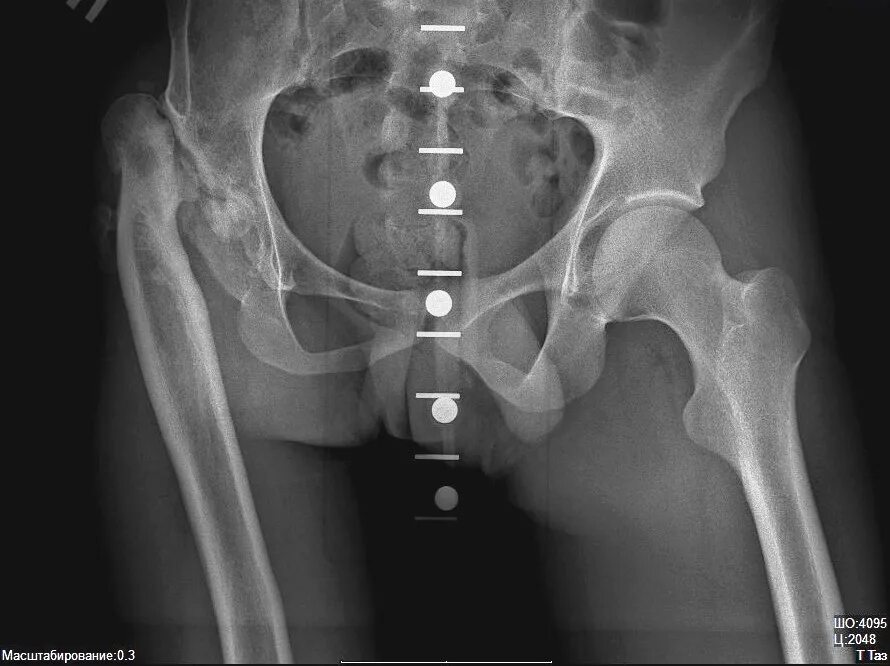

Анкилоз тазобедренного сустава